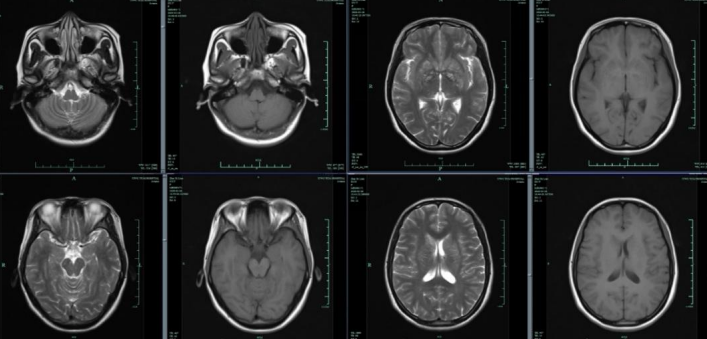

患者9岁,男性。智力低下与发育迟缓。

答案:粘多糖贮积症。MRI可见中度脑积水,第四脑室、大脑导水管、第三脑室和侧脑室明显扩大。大脑萎缩伴脑沟、脑池扩大。有明显的血管周围间隙,伴有脑室周围深层白质筛状征象。粘多糖增多症是一种酶缺乏导致的粘多糖在体内堆积造成的遗传性代谢紊乱。典型临床表现包括骨骼发育畸形,身材矮小,关节僵硬,听力下降,疝气,角膜混浊,青光眼,肝脾肿大,心脏和呼吸系统疾病。头MRI 表现:脑积水与脑萎缩,侧脑室周围白质多发囊状及线状异常信号影,脑灰白质分界不清。骨骼表现包括:椎体前缘呈舌状突出、椎管狭窄(多位于C1/C2节段,原因是齿状突和C1后弓发育不良,继而压迫颈髓交界处,颈髓脊髓病或脊髓空洞症),寰枢椎脱位或半脱位,脊柱后凸,脊柱侧凸,颈椎畸形。Madelung‘s畸形,腕骨体积小,个数减少,近端掌骨呈子弹状,第4掌骨短小。